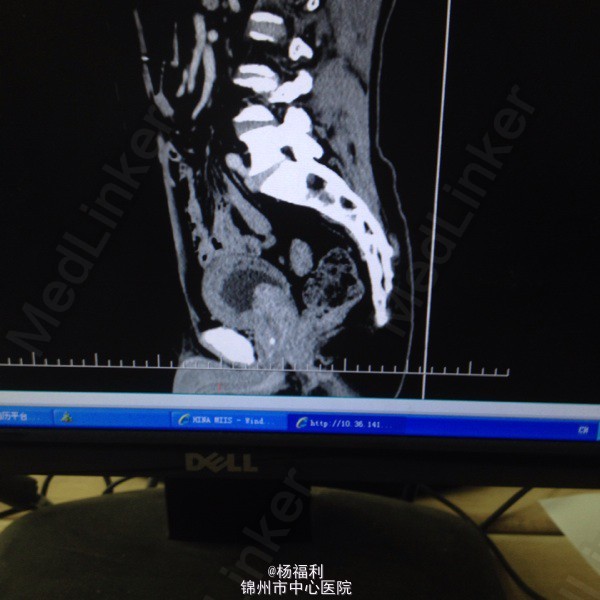

71岁男患,5年前即开始出现尿频,尿急。夜尿3-4次。排尿困难。无发热、无腰痛,无肉眼血尿。一直未与治疗。症状进行性加重。半月前患者排尿困难症状严重,尿滴沥。伴右腰部疼痛来我院就诊。

双肾区无叩击痛。双输尿管走形区无压痛,耻骨上区压痛。叩诊浊音。前列腺指诊前列腺增大,中央沟消失,质韧。未触及硬结及肿物。 彩超;双肾积水,前列腺增大突入膀胱,膀胱肌小梁形成。 ctu:前列腺增生。双侧肾盂及输尿管扩张,左肾多发小囊肿。 膀胱镜:前列腺增大突入膀胱,膀胱内多发小房小梁。 总psa:4.6ng/ml,比值:0.18。 肌酐:175umol/l。 尿常规:白细胞2+。

1、尿潴留2、前列腺增生症3、双肾及输尿管积水4、泌尿系感染。 给予患者留置尿管后择期行经尿道前列腺等离子电切术。 患者家里条件不太好,要求给予快速手术。未等肌酐及积水好转后即给予手术。